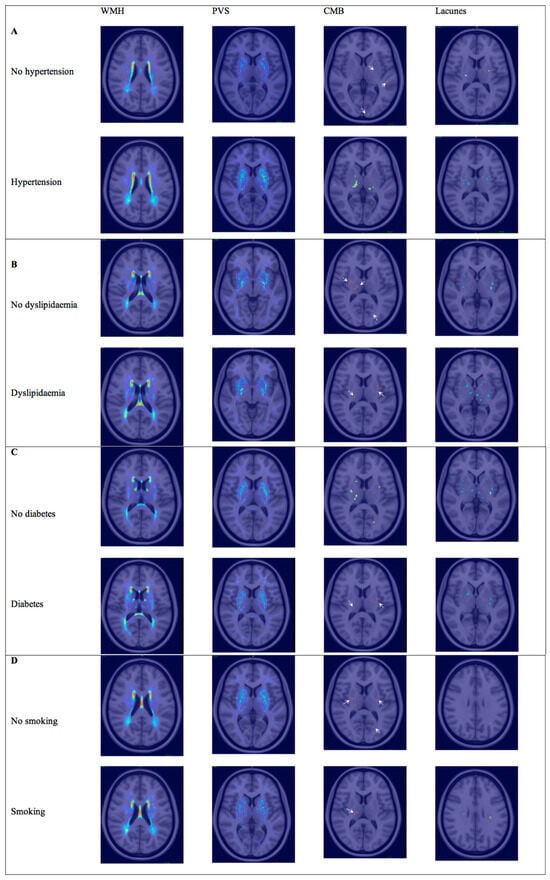

3.1. Hypertension

3.2. Hyperlipidemia

3.3. Diabetes

3.4. Smoking